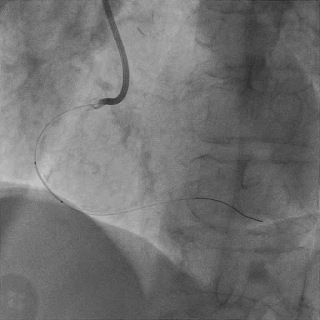

于LAD近中段植入Tivoli 2.75*33mm支架一枚,高压球囊后扩张后,血流TIMI3级

Sion导丝至LCX远端,预扩球囊扩张后,植入支架XIENCEAlpine 2.25*23mm支架一枚

术后造影支架膨胀良好,血流TIMI3级